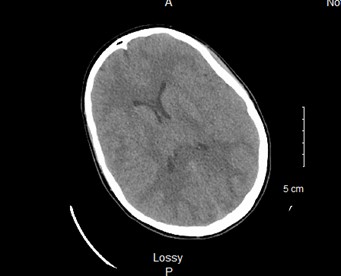

Figure 1. CT head read as small ventricles, effacement of third ventricle and bilateral cortical sulci, suggestive of cerebral edema. No herniation or midline shift. No acute ischemic process or intracranial process.